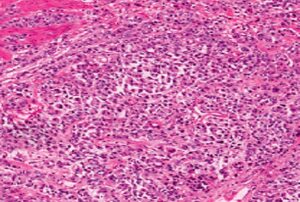

Основная форма онкопроцесса желудка – аденокарцинома. Это означает, что новообразование развилось в железистой ткани, выстилающей внутреннюю часть желудка. Другие виды раковых опухолей включают в себя лимфому, карциному желудка и нейроэндокринную опухоль, но они возникают редко.